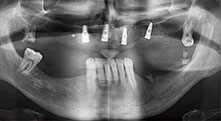

Bratu: We routinely use the instruments for harvesting bone blocks and splitting alveolar ridges. We also use the Piezomed B6/B7 for osteotomy of impacted teeth and removing failed implants. All indications that require deep, clean cuts.

Bratu: We prefer to harvest bone from the external oblique ridge of the posterior mandible, not from the interforaminal region. After the soft-tissue incision, we use the new saws to define the amount of bone to harvest. With this approach, we also use them for the entire preparation in almost 80% of cases. We may also use other piezo instruments and then at the end a chisel to mobilize the block. We find that this is a very effective surgical technique.

Bratu: We like to use the sandwich technique for augmentation in the lateral mandible. A bone cover is prepared with the piezo saw and the crestal fragment is fixed with microscrews. We place a mixture of autologous bone and xenogenic bone replacement material in between. This works very reliably. You should always ensure sufficiently dimensioned vertical cuts when splitting the alveolar ridge in the mandible. Otherwise the bone may fracture easily.

Bratu: I consider piezo surgery a great leap forward in oral surgery. The technique makes bone preparation safer and easier. Little bone is lost, for example in extractions. This is very important in the aesthetic zone, particularly if immediate implantation is planned. Piezo surgery is also safer for soft tissue: injuries to membranes in the sinus are basically history, as are nerve injuries when bone blocks are being harvested. Data indicating reduced postoperative swelling and pain are also available. Piezo surgery is also ideal for preparation of sinus septa. And last but not least, our patients benefit from the atraumatic nature of this technology.